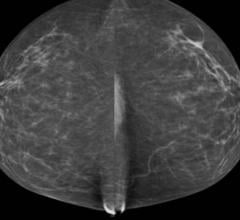

Breast density, or fibroglandular density, is found through breast imaging and compares the amount of fat to the amount of tissue.

Mammography has been the gold standard for breast cancer screening ever since it was proven to reduce mortality in ...

Mammography has long been considered the gold standard for breast cancer detection, acting as the first line of defense ...

As radiologists, most of us have seen firsthand how dense breast tissue can mask cancer in mammography. As breast ...